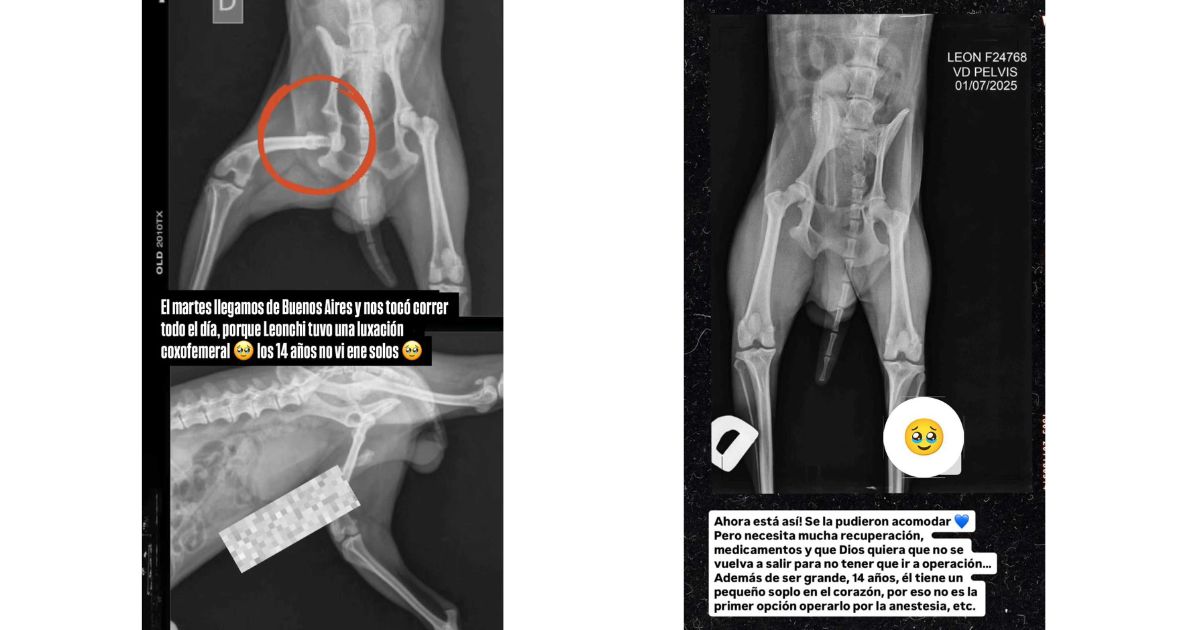

La influencer publicó la foto de una radiografía de su mascota, donde se ve la lesión que sufrió en una de sus extremidades.

“El martes llegamos de Buenos Aires y nos tocó correr todo el día, porque Leonchi tuvo una luxación coxofemoral. Los 14 años no vienen solos”, escribió sobre la imagen.

En una siguiente radiografía, mostró que le pudieron acomodar la pata, pero “necesita mucha recuperación y medicamentos”.

“Que Dios quiera que no se vuelva a salir para no tener que ir a operación. Además de ser grande (14 años), tiene un pequeño soplo al corazón, por eso no es primera opción operarlo por la anestesia”, explicó Euge.